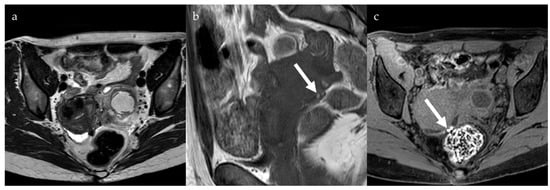

2.1. Endometrioma

2.2. Deep Pelvic Endometriosis